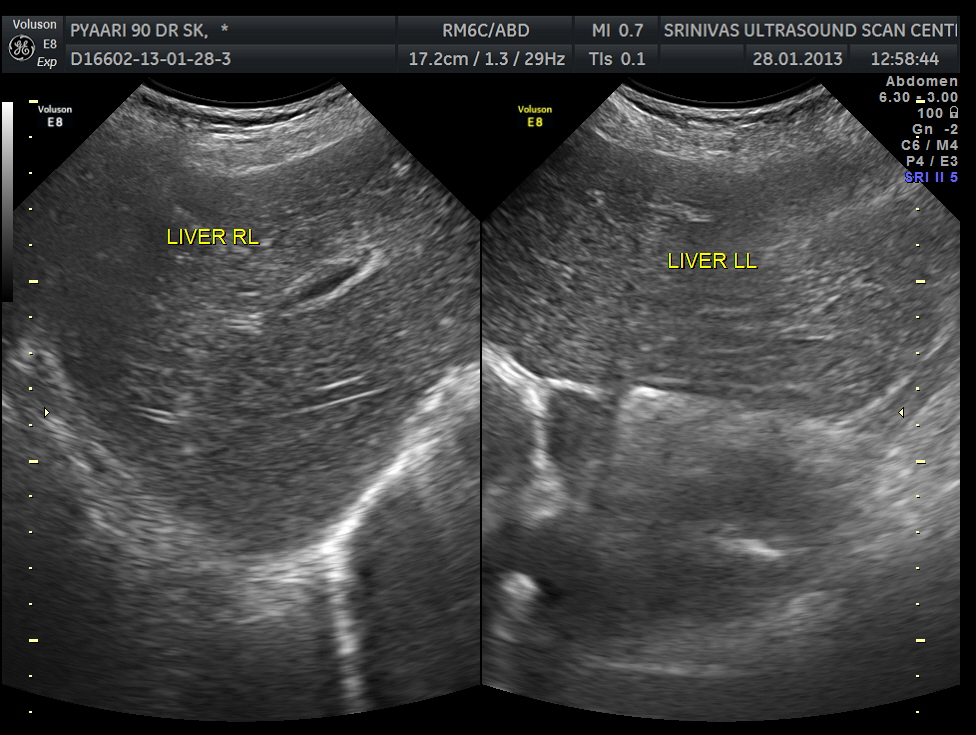

No obvious liver secondaries seen.